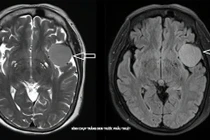

Bệnh nhân đau đầu nhẹ kéo dài, chụp CT và MRI, các bác sĩ phát hiện khối u màng não lớn, vị trí sàn sọ phức tạp cần can thiệp phẫu thuật.

Ngày 5/9, Bệnh viện Đa khoa Thủ Đức cho biết, các bác sĩ vừa điều trị thành công một ca u màng não phức tạp cho bệnh nhân lớn tuổi có nhiều bệnh nền.

Bệnh nhân P.T.N, 73 tuổi, ngụ tại phường Tam Bình, TP HCM, được phát hiện khối u màng não thái dương trái kích thước 3,5x5cm sau khi đi khám vì triệu chứng đau đầu kéo dài.